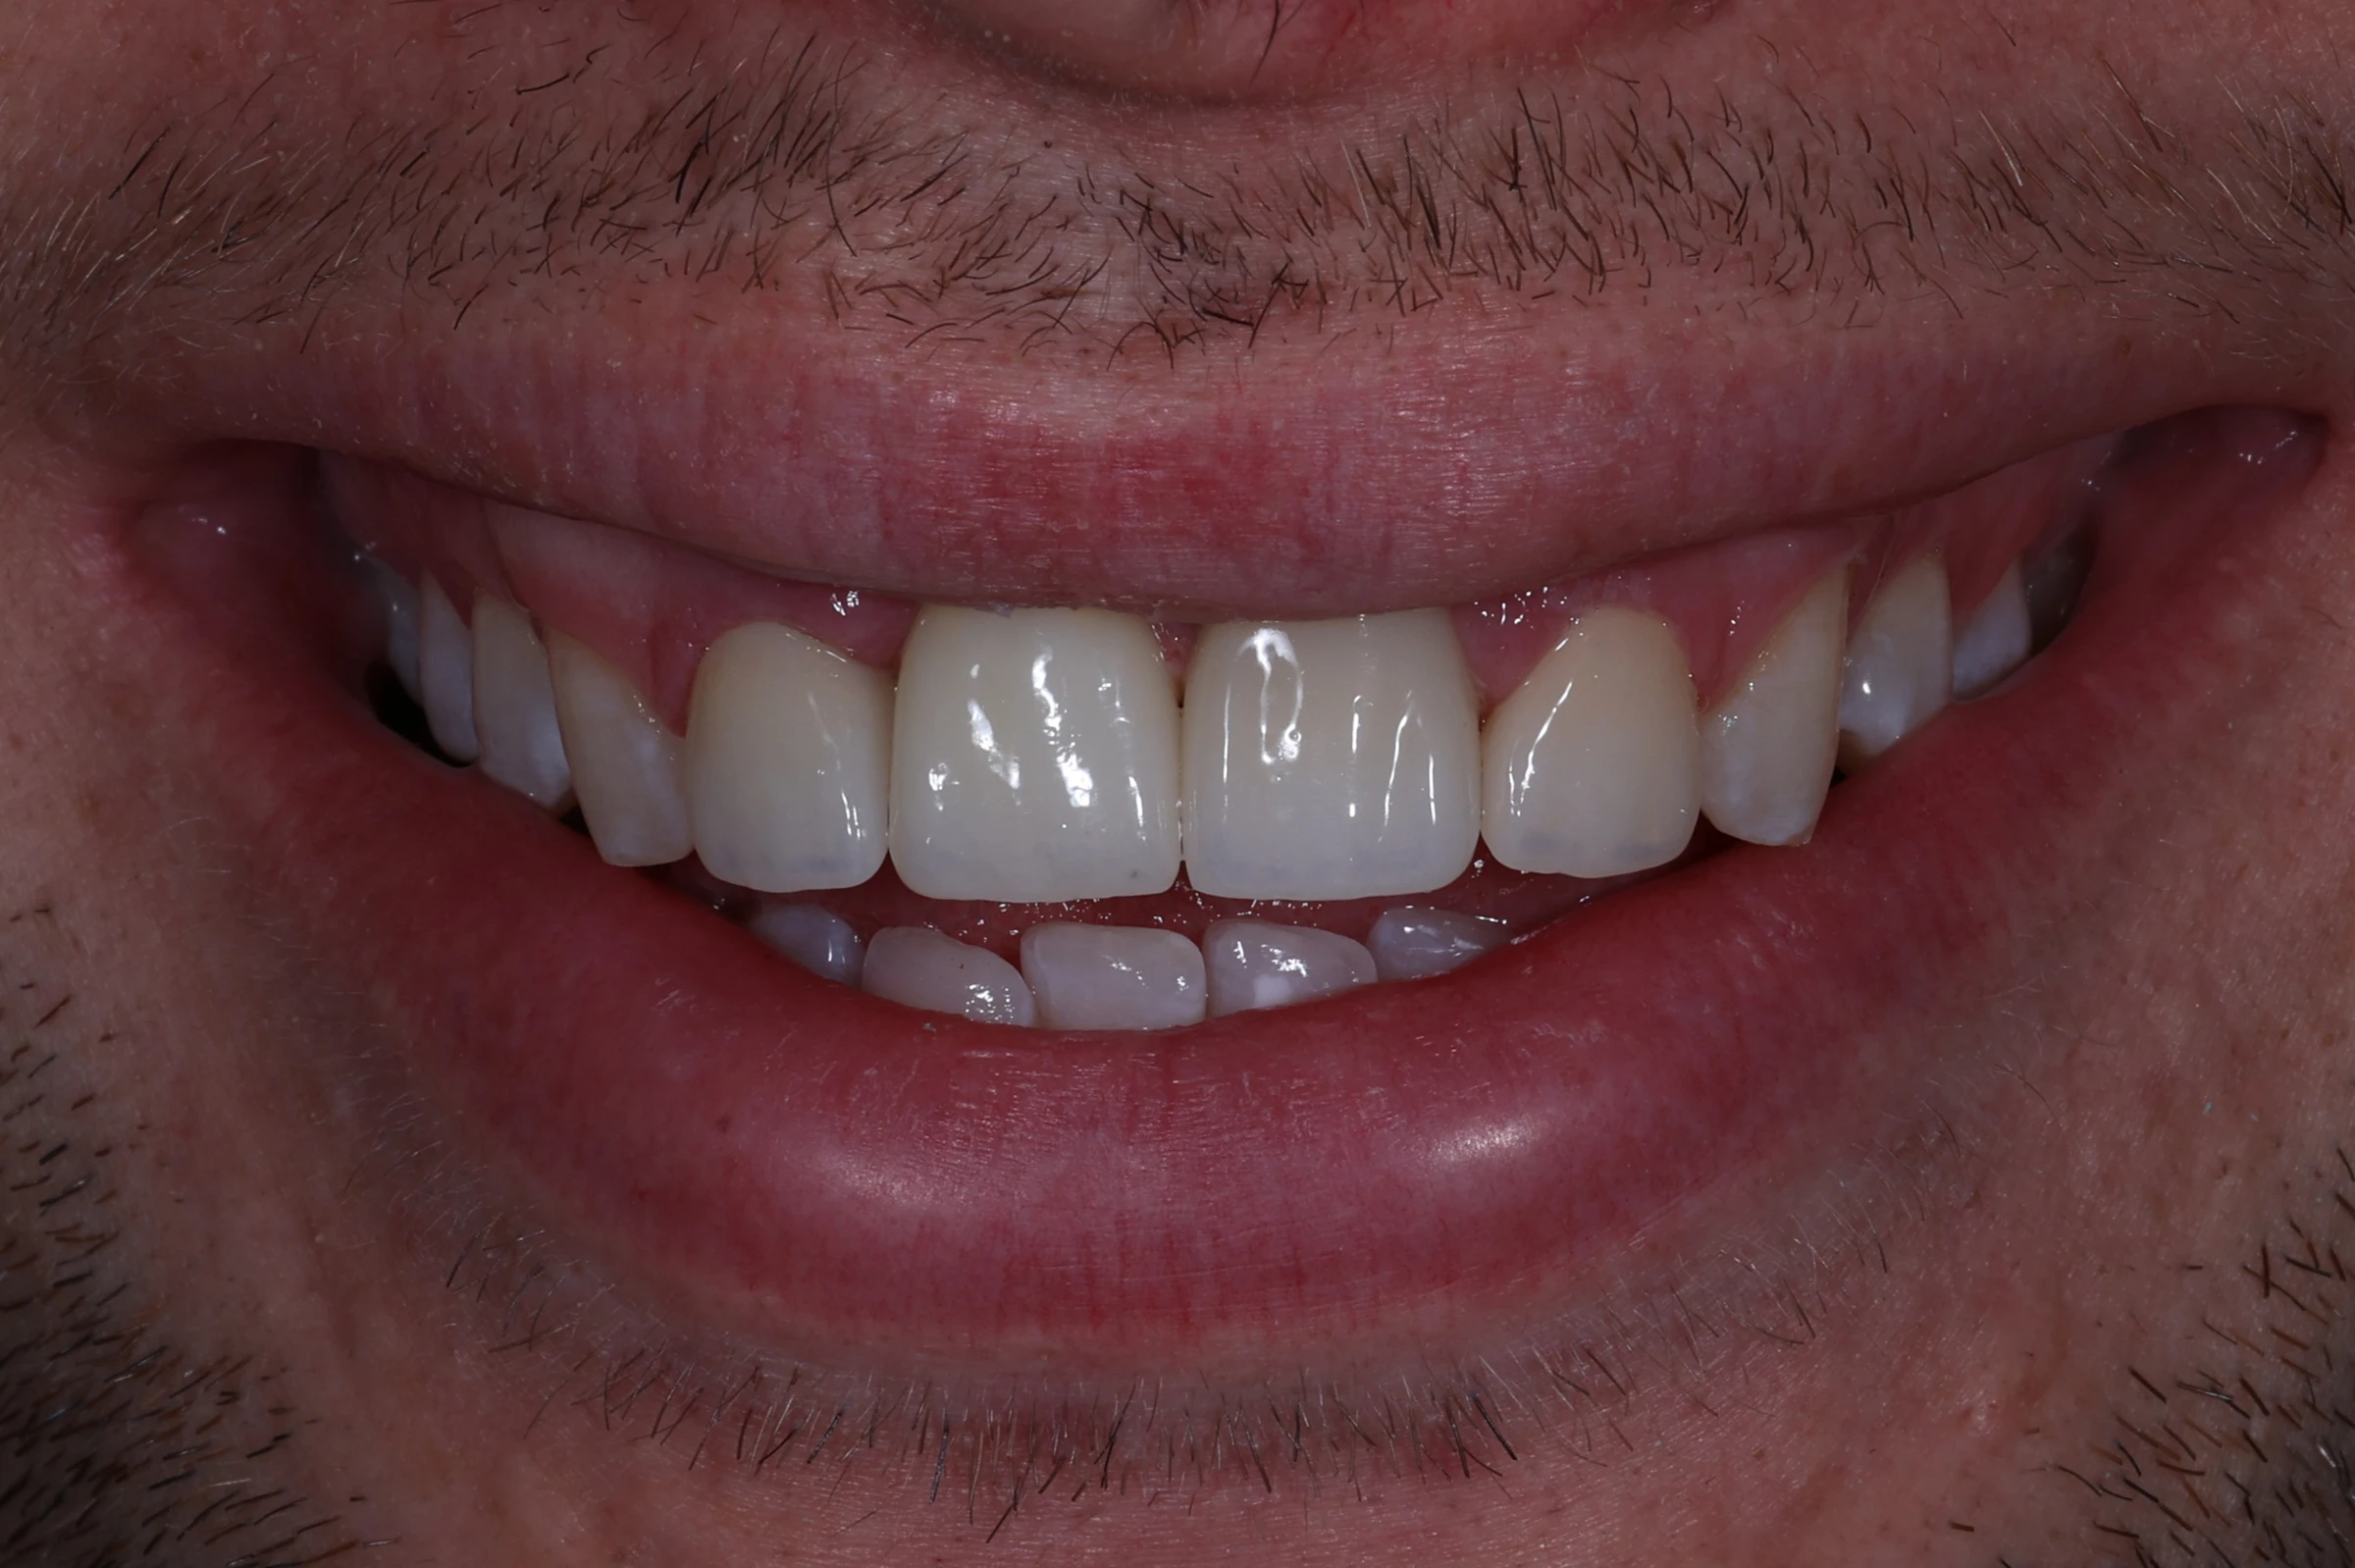

Rezultatul final

Zâmbet complet și natural

Incisivul frontal refăcut perfect integrat estetic în arcadă

Funcție fonetică restabilită

Pronunție corectă și confort în comunicare

Rezultat durabil

Coroană din zirconiu pe implant, rezistentă și stabilă pe termen lung

Reconstrucția unui incisiv frontal este una dintre cele mai delicate proceduri în implantologie estetică. Am realizat o regenerare osoasă ghidată și o coroană perfect adaptată culorii și formei dinților vecini. Rezultatul final a depășit așteptările pacientului, oferindu-i un zâmbet natural și simetric.

Pușcașu Octavian, medic stomatolog chirurg